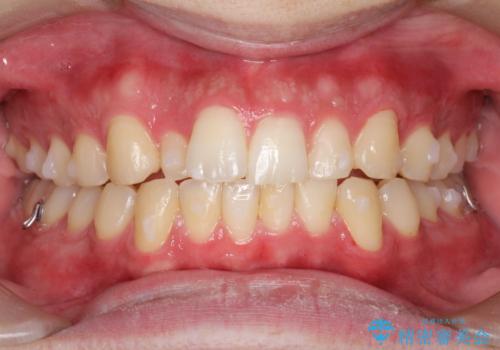

- 前歯の歯並びの改善を希望され来院された患者様です。

初診時の歯並びの状態としては、上下ともに前歯部の中等度以上のがたつき(叢生)があり、右の前歯が1本飛び出した状態でした。

抜歯は行わず上下顎ともに、主に歯列弓の拡大とディスキング(歯と歯の間に隙間を作る処置)を行い叢生を改善しました。